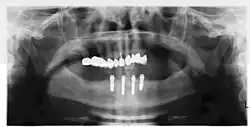

Fixní můstek s implantátem nebo můstek s implantátem

Můstek podepřený implantátem (nebo fixní zubní náhrada) je skupina zubů upevněných na zubních implantátech, takže uživatel nemůže protézu sundat. Jsou podobné běžným můstkům s tím rozdílem, že protéza je podepřena a upevněna jedním nebo více implantáty namísto přirozených zubů. Můstky se obvykle připojují k více než jednomu implantátu a mohou se také připojovat k zubům jako kotevní body. Obvykle počet zubů převyšuje počet kotevních bodů, přičemž zuby, které jsou přímo nad implantáty, se označují jako pilíře a zuby mezi pilíři se označují jako mezičleny. Můstky podporované implantáty se připevňují k pilířům stejným způsobem jako náhrada jednoho zubu implantátem. Fixní můstek může nahradit i pouhé dva zuby (známý také jako fixní částečná zubní náhrada) a může se rozšířit a nahradit celý zubní oblouk (známý také jako fixní úplná zubní náhrada). V obou případech se o protéze říká, že je fixní, protože ji nositel nemůže sundat.[12]

Protetické postupy u snímatelných zubních náhrad

Při nošení snímatelné zubní náhrady mohou být fixátory, které drží zubní náhradu na místě, vyrobeny buď na zakázku, nebo jako "hotové" (skladové) abutmenty. Při použití zakázkových fixátorů se umístí čtyři nebo více implantáty, pořídí se otisk implantátů a v zubní laboratoři se vytvoří zakázková kovová tyč s nástavci, která drží zubní náhradu na místě. Výraznou fixaci lze vytvořit pomocí více nástavců a použitím polopřesných nástavců (například čepu malého průměru, který se protlačí skrz zubní náhradu do tyče), což umožňuje malý nebo žádný pohyb zubní náhrady, která však zůstává snímatelná.[14]:s.33–34 Stejné čtyři implantáty nastavené pod takovým úhlem, aby rozkládaly okluzní síly, však mohou bezpečně udržet fixní zubní náhradu na místě se srovnatelnými náklady a počtem zákroků, což nositeli zubní náhrady poskytne fixní řešení.[45]